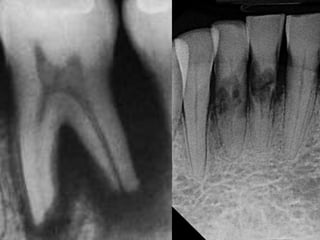

Periapical Condition Tooth Related

Contended

Contraindications

Referral might be

required

Not an absolute

contra-indiction